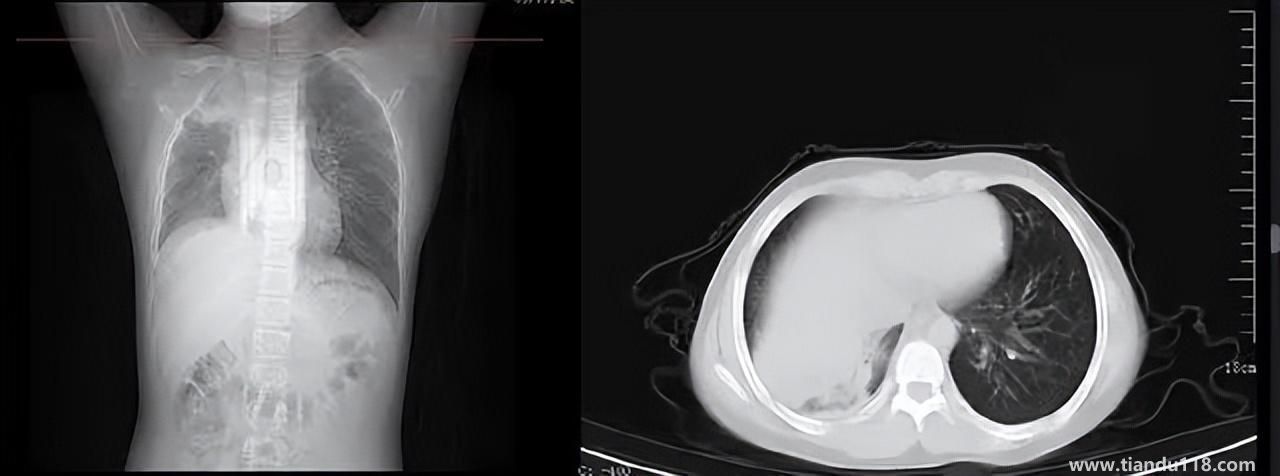

男孩咳嗽發(fā)熱在家硬扛成白肺(醫(yī)生表示以下幾種情況別硬“扛”) 男孩咳嗽發(fā)熱在家硬扛成白肺(醫(yī)生表示以下幾種情況別硬“扛”) 近日,一名12歲男孩咳嗽一周不就醫(yī),一側(cè)肺部“扛”成了“白肺”?!氨е鴥e幸心理一直在家硬‘扛’,沒(méi)想到‘扛’出這么重的?。 焙⒆蛹议L(zhǎng)悔不... 小編 2022-12-28 939

感染新冠會(huì)變白肺?醫(yī)生:有年輕病例 感染新冠會(huì)變白肺?醫(yī)生:有年輕病例感染新冠會(huì)變白肺嗎?對(duì)此,有專(zhuān)家表示,造成“白肺”情況有很多種,感染新冠只是一種可能。少量患者肺有滲液 ,咳嗽不會(huì)引發(fā)白肺,有年輕人病例。... 小編 2022-12-27 608

3個(gè)辦法可提前預(yù)警白肺(咋預(yù)防“白肺”) 3個(gè)辦法可提前預(yù)警白肺(咋預(yù)防“白肺”)家里有老人,擔(dān)心出現(xiàn)“大白肺”、“沉默型缺氧”等情況,具體如何應(yīng)對(duì),提前預(yù)警?近日,大象新聞接到諸多咨詢(xún)。針對(duì)這些問(wèn)題,大象新聞?dòng)浾咦隽硕喾讲稍L(fǎng)。什么是白肺?對(duì)... 小編 2022-12-28 693

白肺與原始毒株和疫苗接種沒(méi)關(guān)系(國(guó)家衛(wèi)健委表示) 白肺與原始毒株和疫苗接種沒(méi)關(guān)系(國(guó)家衛(wèi)健委表示)從近期的公眾反映情況看,有的新冠病毒感染者在就診過(guò)程中發(fā)現(xiàn)了肺炎或者是CT出現(xiàn)了白肺的現(xiàn)象,有網(wǎng)友認(rèn)為,出現(xiàn)這種情況可能是跟感染了原始毒株或者接種疫苗有... 小編 2022-12-28 530

為何有人出現(xiàn)“白肺”?專(zhuān)家回應(yīng)和疫苗接種無(wú)關(guān) 為何有人出現(xiàn)“白肺”?專(zhuān)家回應(yīng)和疫苗接種無(wú)關(guān)國(guó)務(wù)院聯(lián)防聯(lián)控機(jī)制12月27日召開(kāi)新聞發(fā)布會(huì),針對(duì)有媒體提問(wèn)稱(chēng),從近期公眾的反映情況看,有的新冠病毒感染者在就診過(guò)程中發(fā)現(xiàn)了肺炎或者是CT出現(xiàn)了“白肺”的現(xiàn)... 小編 2022-12-27 817